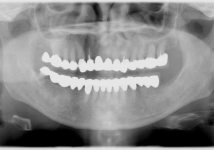

レントゲン写真

<症例2>60歳代 男性

長年放置したために歯周病が進行し噛みにくくなった患者様が、インプラントを入れ全顎的な治療を行い、審美改善しました。